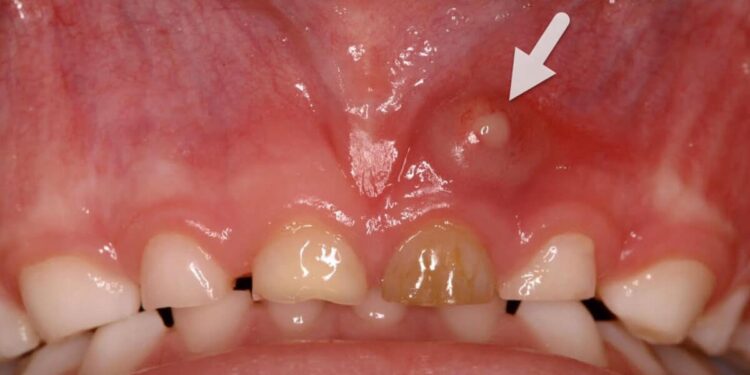

A dental abscess, also known as a tooth abscess, is a localized collection of pus caused by a bacterial infection in or around the tooth. According to the Mayo Clinic, it is essentially a pocket of pus that forms due to bacterial invasion, typically in the dental pulp, the innermost part of the tooth containing nerves, blood vessels, and connective tissue.

The Cleveland Clinic describes an abscess as a red, swollen bump, boil, or pimple-like formation in the gums, resulting from the body’s immune response to trap and fight the infection. If not addressed, the infection can spread beyond the mouth, leading to systemic issues.